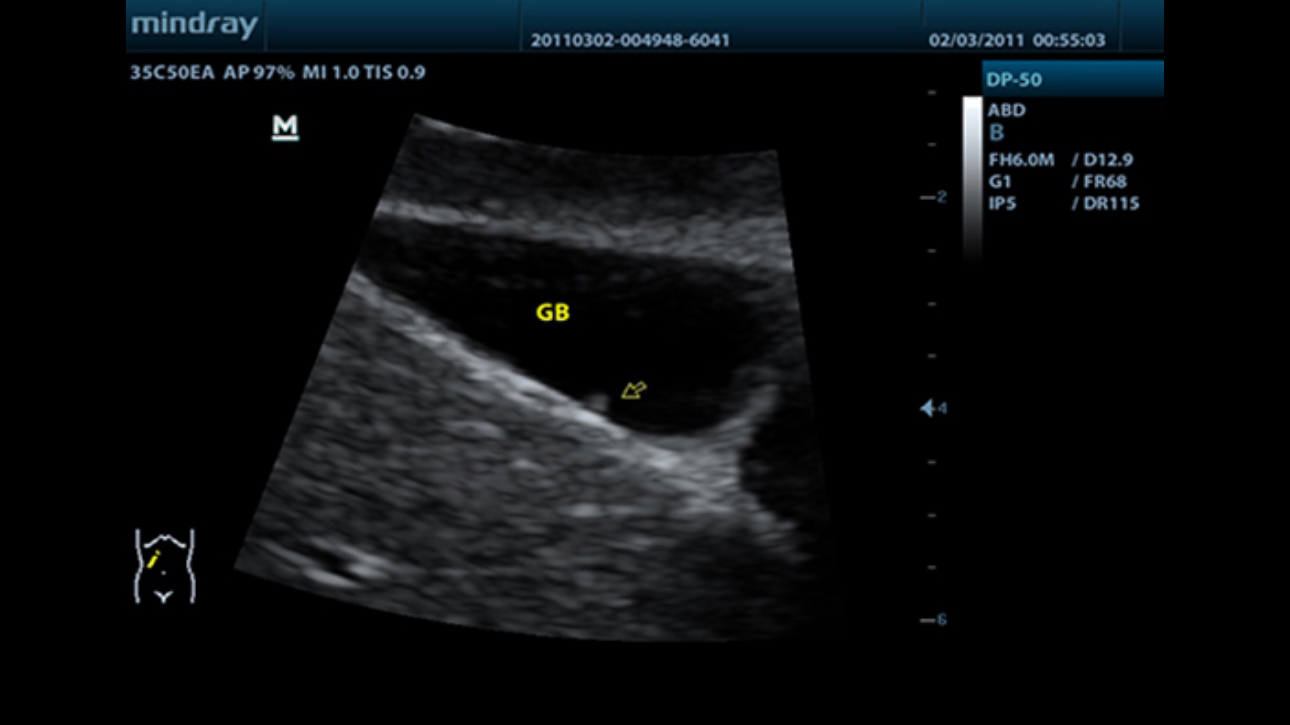

DP-50

MindrayŌĆÖs new generation of black & white ultrasound system, DP-50, is equipped with advanced imaging technologies allowing deeper penetration and faster image acquisition with higher resolution.? A smart new shape, enhanced mobility and convenient operation make DP-50 well suited for all clinical settings.